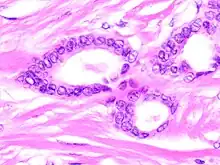

Tubular carcinoma is a subtype of invasive ductal carcinoma of the breast.[2][3] More rarely, tubular carcinomas may arise in the pancreas[4] or kidney.[5] Most tubular carcinomas begin in the milk duct of the breast and spread to healthy tissue around it.[6][7]

Although tubular carcinoma has been considered a special-type tumor,[lower-alpha 1] recent trend has been to classify it as a low-grade, invasive NOS carcinoma because there is a continuous spectrum from pure tubular carcinomas to mixed NOS[lower-alpha 2] carcinomas with tubular features, depending on the percentage of the lesion that displays tubular features.[10]: 647

Tubular carcinomas are generally around 1 cm. or smaller, and are made up of tubules. They are usually low-grade.[2] Elastosis has been noted as common but is not present in all cases.[11]

A highly differentiated invasive carcinoma that forms well-defined tubules (containing epithelium, but no myoepithelium) and that have abundant desmoplastic fibrous stromal reaction between the tubules.